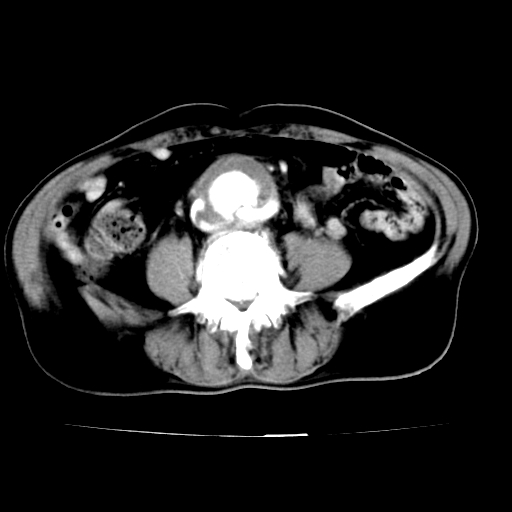

给平扫片看看血管壁钙化情况。

作者: sunhua666    时间: 2007-5-25 03:22

此病例平扫图像已发,请大家看看!